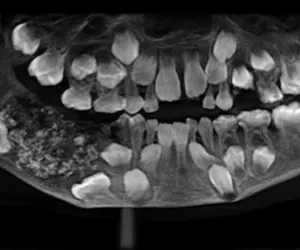

Henüz 7 yaşında olan P. Ravindran, ilk olarak alt çenesindeki ağrı ve şişlikten şikayetçi olarak ailesiyle hastaneye gitti. Ancak doktorlar karşılaştıkları görüntü karşısında şaşkına döndü. Hekimlerin incelemesi sonucu küçük çocuğun ağzında fazladan dişler içeren “torba benzeri” bir tümör bulundu.